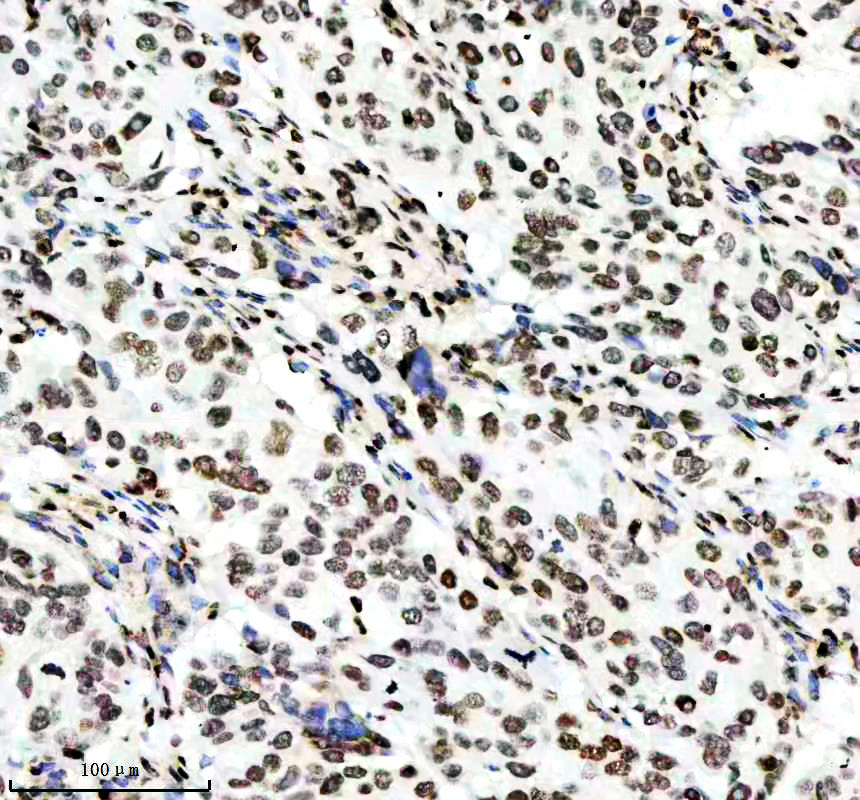

IHC analysis of Histone H3 (acetyl K14) using anti-Histone H3 (acetyl K14) antibody (BM4151) .

Histone H3 (acetyl K14) was detected in a paraffin-embedded section of human rectal cancer tissue. The tissue section was incubated with rabbit anti-Histone H3 (acetyl K14) Antibody (BM4151) at a dilution of 1:200 and developed using HRP Conjugated Rabbit IgG Super Vision Assay Kit (Catalog # SV0002) with DAB (Catalog # AR1027) as the chromogen.

IHC analysis of Histone H3 (acetyl K14) using anti-Histone H3 (acetyl K14) antibody (BM4151) .

Histone H3 (acetyl K14) was detected in a paraffin-embedded section of human rectal cancer tissue. The tissue section was incubated with rabbit anti-Histone H3 (acetyl K14) Antibody (BM4151) at a dilution of 1:200 and developed using HRP Conjugated Rabbit IgG Super Vision Assay Kit (Catalog # SV0002) with DAB (Catalog # AR1027) as the chromogen.